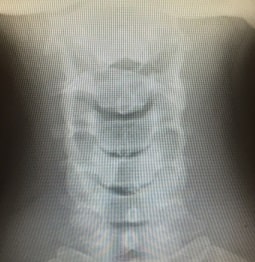

首の筋肉の突っ張りを伴った激しい頭痛、発熱、吐き気、嘔吐、意識の混濁、など。